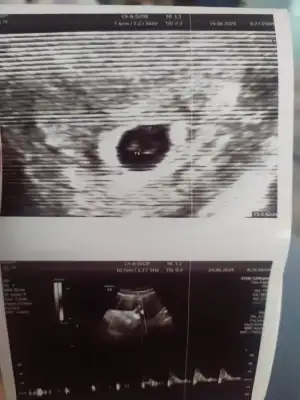

Kızlar merhaba, bu da benim miniğim karından ultrason fotoğrafları 9+4 deyiz. Tahminde bulunabilir misiniz 🥰

Eklentiler

• IMG_2428.webp

IMG_2428.webp

81,6 KB · Görüntüleme: 89

• IMG_2429.webp

IMG_2429.webp

70,8 KB · Görüntüleme: 83